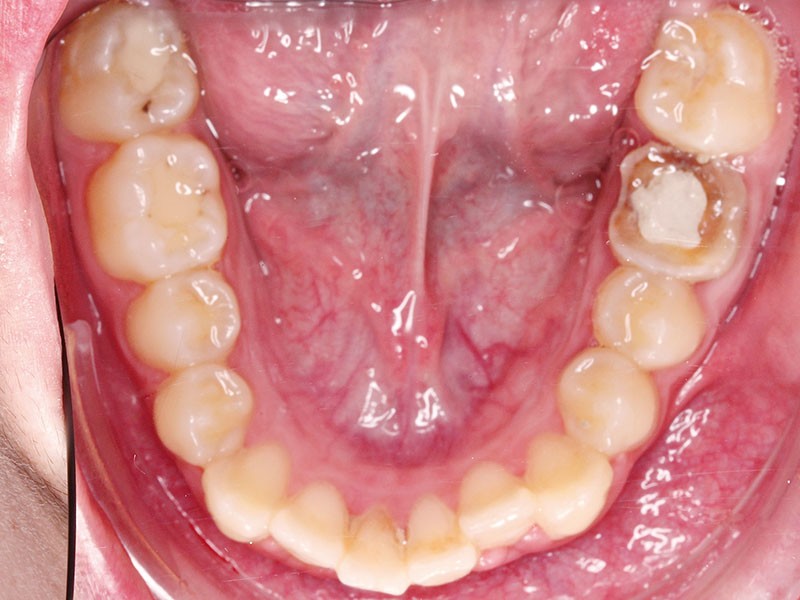

• Endo-buccal : Younesse présente un contrôle de plaque dentaire insuffisant, la persistance de 53 et 63, des soins en cours de réalisation sur 26 et 36, un encombrement maxillo-mandibulaire avec infravestibulotopie de 23 et une suspicion d’inclusion de 13 sur un schéma de Classe II subdivision droite (fig. 3 à 7).

L’examen parodontal révèle une gingivite généralisée ainsi qu’un parodonte très fin et une absence de profondeur vestibulaire.